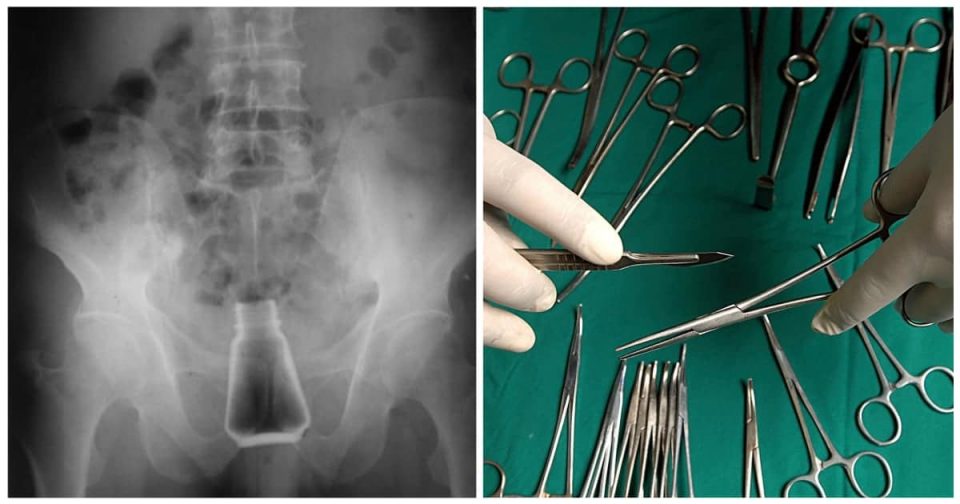

Ο ασθενής μεταφέρθηκε εσπευσμένα στο νοσοκομείο της Σύρου, καθώς κινδύνευε η ζωή του.

Αμέσως, ο ασθενής μπήκε στο χειρουργείο και του αφαιρέθηκε το αντικείμενο που υπήρχε στον πρωκτό του, προτού υπάρξουν πιο δυσάρεστες συνέπειες για την υγεία του.